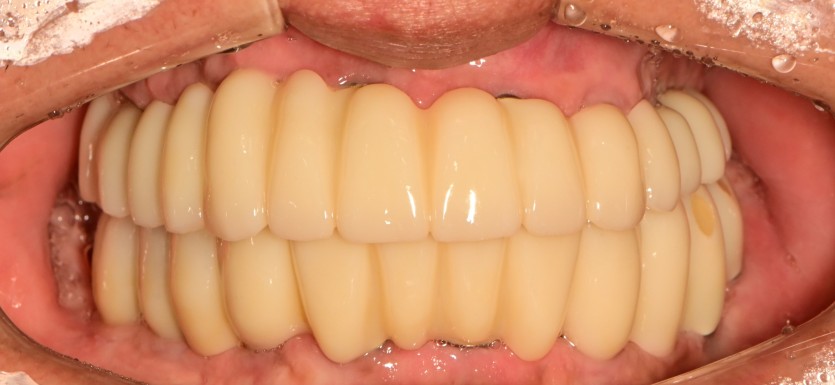

만 58세 전체 임플란트 증례

전체 임플란트 증례입니다.

18개의 임플란트로 완성하였습니다.